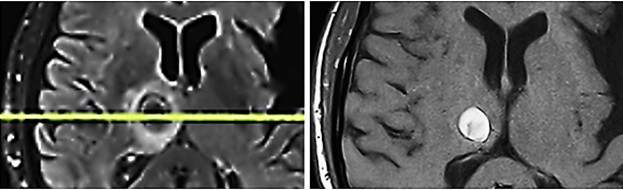

Fig. 5

Fig. 5: Metastasis in the right thalamus before transcranial TMI treatment with pronounced perifocal edema (left) and five months after TMI treatment; notably the brain tissue is not impaired by the transcranial TMI treatment (right).

August 2025

After transcranial TMI treatment as described, the patient was becoming increasingly alert and showed improvement in all neurological investigations. With the support of the physiotherapist, he could now walk short distances and climb one flight of stairs, use the toilet independently, his spatial awareness was steadily improving, he could eat independently, and had complete recollection of all events up to the onset of somnolence. He had no memory of the eight weeks of somnolent state. A follow-up MRI of the skull shows the previously identified hemorrhagic area surrounded by a glial capsule and a perifocal edema, but no further progression of the metastasis. The TMI reated thalamic metastasis had shrunk considerably though it is unsure if there remained still vital tumorous tissue (Fig. 5). It must be underlined that the surrounding brain tissue was not impaired or damaged by TMI treatment, so that the patient clinically improved, unexpectedly gained again full neurological control, could leave the hospital and return home.